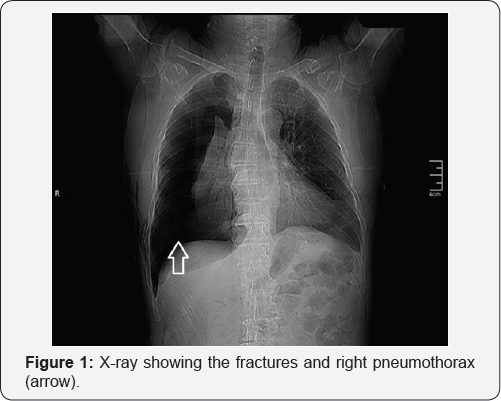

Admission X-ray and computed tomography showed fracture extreme axis deviation to the right and tall R-wave in V1 suggesting at the sixth, seventh and eighth right costal arches with significant right-ventricle overload (Figure 3). right pneumothorax (Figure 1 & 2). ECG showed low voltage,